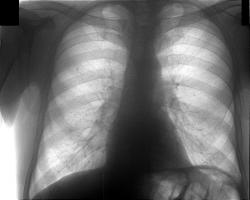

Через 10 дней направлен повторно, диагноз - пневмония слева. Прямой снимок без признаков инфильтрации, учитывая клинику (интоксикация, гектическая температура, боль в лев. половине гр. кл.), решили посмотреть за сердцем в лев. косом положении, лев. боковой сам Бог велел (снимки представлены). Посмотрели и скопически: в S10 инфильтрация с участками просветления, в заключении написали - пневмония, но термин "абсцедирование" решили не применять, хотя "в уме держали". Больного направили в т/о, там почему-то усомнились в нашей диагностике, пациент вернулся: "меня направляют на Р-гр". Пришлось связаться с терапевтами и прочитать лекцию о том, кто и за что отвечает. На следующий день терапевты с завидным упрямством настаивают на контрольной Р-гр., говорят - боимся абсцедирования, хорошо - говорю, договариваюсь с кэтэшниками, "прокатили" грудную клетку. Но ничего нового, дополнительного не нашли, а "просветлениями" оказались просветы бронхов. Инфильтрация расположена пристеночно, прилежит к позвоночнику с переходом на заднюю стенку гр. клетки, именно в связи с этим никак не прявляет себя на прямом снимке и на боковом выглядит не слишком убедительно. Наиболее оптимальными для такого расположения являются передняя левая или задняя правая косые проекции. Еще через 10 дней, при контрольной рентгеноргафии (прямая и левая боковая), картина без признаков инфильтрации, зная особенности случая, беру за экран и при указанных выше положениях вижу остатки инфильтрации, трактую как "остаточные изменения после пневмонии". Клинически - пациент бъет себя в грудь: "все прекрасно, домой хочу!".

Сие наблюдение нашего коллеги врача - рентгенолога В.Б. Серова весьма показательно по следующим обстоятельствам: 1. В настоящее время во многих лечебных учреждениях, как среди врачей клиницистов, так и среди части врачей рентгенологов, бытует мнение, что рентгеноскопия – рентгенотелевидение, при исследовании пациентов с «легочной патологией» себя изжило, и в ряде лечебных учреждений данные исследования отданы в руки рентгенолаборантов, а врачи рентгенологи на следующий день «пишут рентгенографическую продукцию» (я ещё раз подчеркиваю, что «в ряде лечебных учреждений». И очень отрадно, что врачи – рентгенологи, используя полипозиционную рентгеноскопию – рентгенотелевидение обоснованно безусловно, как демонстрирует данный случай (за сердечной тенью) визуализируют паторлогический процесс, который задокументирован на левой боковой рентгенограмме. 2. Довольно типично для врачей терапевтов, да и врачей хирургов, что свидетельствует об отсутствии этики и деонтологии, а также о коллегиальности, «усомниться в заключении рентгенолога». Чаще всего это связано с амбициями, а в ряде случаев, что встречается более часто с потерей именно терапевтами навыков аускультации, перкуссии, и нежелании инспектировать больного согласно принятой схеме стандарта. И что интересно терапевты считают, что они очень хорошо разбираются в рентгенологии и вообще «параклинике» и также «не доверяют» врачам лаборантам, но почему – то стекол не пересматривают, а вот рентгенограмму «посмотреть» на фоне окна и деревьев, видимых из этого окна – весьма эффектно, особенно, когда рядом находится пациент. 3. Очень интересная тактика обследования на следующий день на КТ, а не в динамике (это безусловно свидетельство безалаберности и попустительства начмеда). В связи с этим немного в сторону – мне очень нравятся врачи КТ и их разновидности, которые перед исследованием ОГК, требуют произведенные в рентген-кабинете снимки- рентгенограммы и линейные томограммы. Интересно зачем, если КТ-шные методики считаются более информативными. 4. Уважаемый коллега! Я с Вами не соглашусь, что на левой боковой рентгенограмме инфильтрация выглядит неубедительно, по – моему довольно убедительно, но конечно это субъективно. 5. С Вами невозможно не согласиться, по поводу остаточных изменений, и довольно часто, как вы указываете, мы наблюдаем «фрагменты ранее определявшейся инфильтрации», что даже в нашей литературе трактуется, как «остаточные явления», хотя каждый рентгенолог прекрасно понимает, что до восстановления структуры еще далеко. То что в данный период терапевты «уже ничего не слышат» - все хорошо, не говорит ни о чем, они весьма часто и стадиях опеченения «ничего не находят».